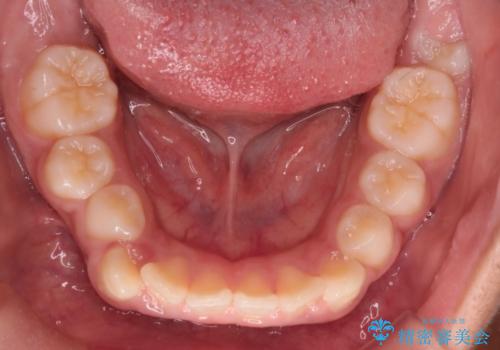

まず、上顎にリンガルアーチを装着し、歯列の幅を適正に維持しながら遠心移動をサポート。さらに、**TAD(矯正用アンカースクリュー)**を利用することで、奥歯を固定源とせずに前歯だけを後方へ移動させることが可能になりました。これにより、抜歯をせずに前歯の突出を抑え、バランスの取れた口元へと改善。治療後、患者様からは「抜歯せずに理想の仕上がりになり、大満足」とのお声をいただきました。